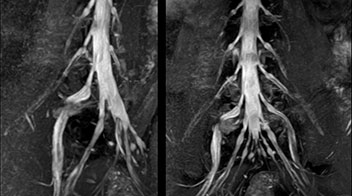

Because the obtained NerveVIEW images often exhibit a high signal in the intervertebral discs, we use partial MIP images to eliminate such intervertebral disc high signals. MIP image generation is based on the  center of the coronal stack, and RAO (right anterior oblique) and LAO (left anterior oblique) images rotated in the range of 45 degrees are used for diagnosis.

Implementing NerveVIEW without lengthening exam time

3D NerveVIEW3D NerveVIEWT2W sagittal and axial

T1W sagittal and axial

3D NerveVIEW

T2W sagittal and axial

Routine lumbar spine MRI

(without neurography)

Fat suppressed T2W coronal